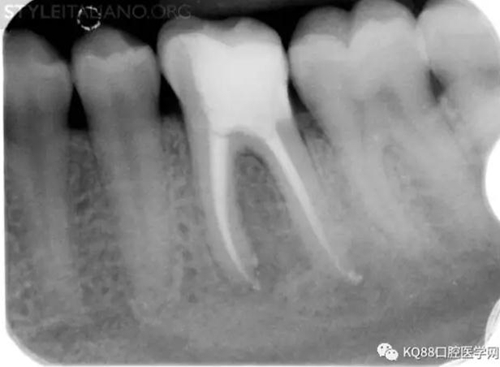

Img. 2 - Retreatment of distal canal was performed using ProTaper retreatment files. Working length was assessed electronically. Canal was shaped with a Reciproc R40, thoroughly irrigated with US activation, filled with corresponding Guttafusion obturator. Pain disappeared completely some days after retreatment. In all likelihood, incomplete preparation allowed residual pulp tissue to remain in the root canal, acting as an irritant.